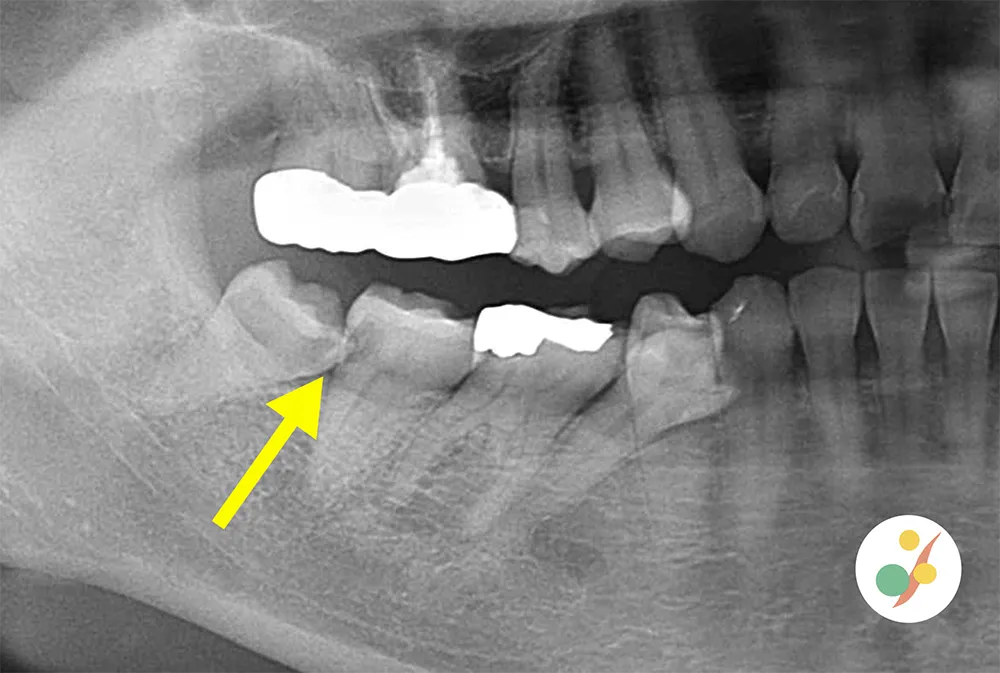

親知らず

親知らずは真っ直ぐ生えていることはあまりありません。そのため汚れが溜まりやすく、写真の様に隣の歯に大きな虫歯を作ってしまいお口の環境にい大きく影響を与えてしまうこともあるため、問題を起こしそうな場合は抜歯を勧めています。